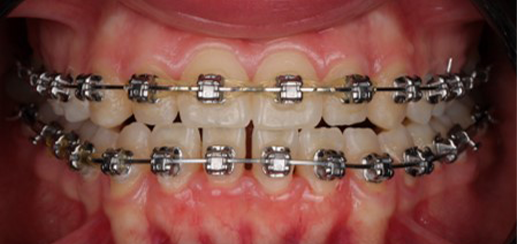

Initial leveling in the maxillary arch was carried out with a 0.014 CuNiTi archwire. This was followed by a 0.018 CuNiTi wire, with stoppers positioned mesial to the molars and activated to provide protrusion of incisors. The mandibular arch was then bonded and initial alignment was achieved with a 0.014 CuNiTi wire, then both jaws are progressing to 0.014 × 0.0275 CuNiTi and subsequently 0.018 × 0.0275 CuNiTi for torque control.